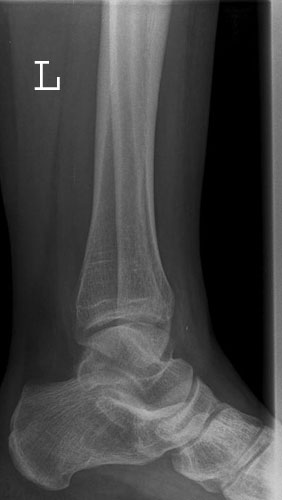

OSG seitlich

132_4.jpg

Fehler

Doppelkonturierung im oberen Teil der Talusrolle. Die Beurteilung des OSG ist nicht möglich. Die Spitze des Malleolus lateralis steht höher als die Spitze des inneren Malleolus.

Abhilfe

Der Fuß muss gesamthaft etwas höher gelagert werden, bei streng seitlicher Zentrierung.